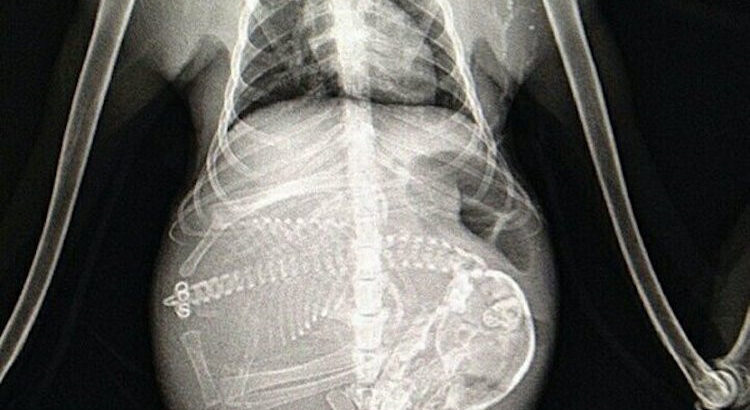

Le saviez-vous ? Le raton laveur est une espèce de mammifères omnivores qui doit son nom à son habitude, pas totalement vérifiée, de tremper ses aliments dans l’eau avant de les manger. Il est facilement reconnaissable grâce à son masque de poils noirs autour des yeux. Les femelles ne peuvent se reproduire qu’une fois par an et leur gestation dure 63 jours (les veinardes).

Une portée comprend entre un et trois ratonneaux pour les espèces vivant au sud contre trois à sept pour celles vivant au nord. Les jeunes naissent aveugles et ce sont les ratonnes qui s’occupent seules de leur élevage pendant leurs quatre premiers mois. Le fameux masque noir apparaît un peu avant leurs dix semaines.